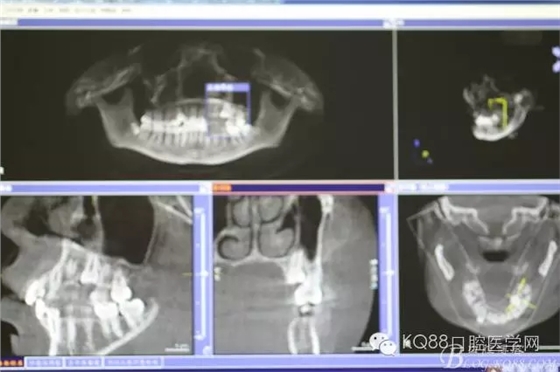

圖4.CBCT三維影像顯示:25位于24與26之間的腭側